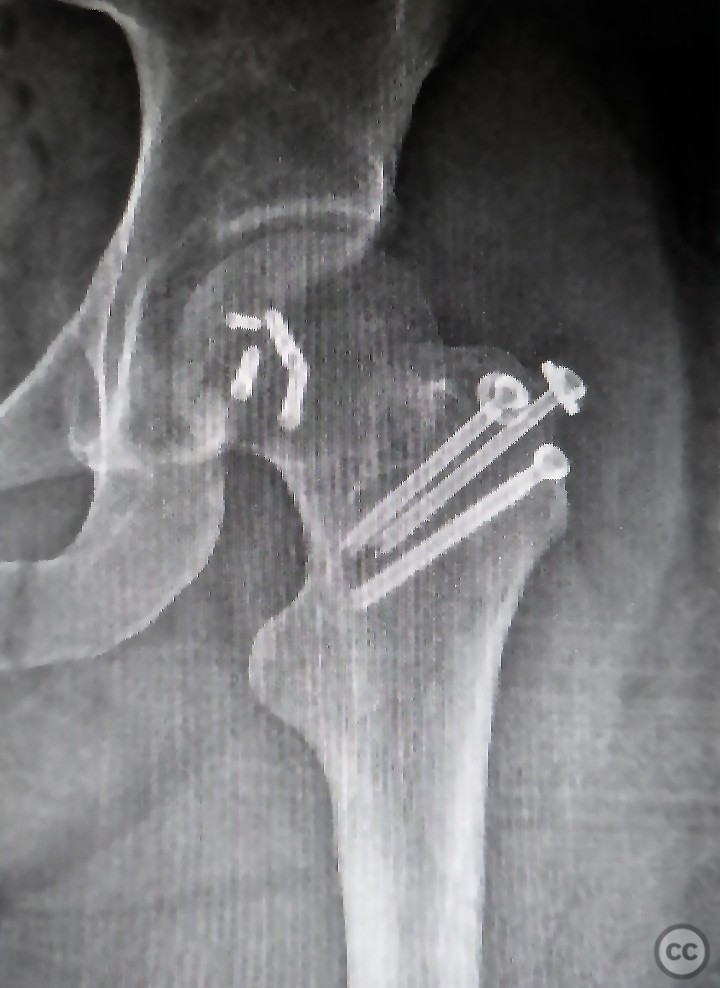

Nov 27 2022

By orthopaedic_trauma

Pipkin 2 + cranial peripheral acetabular...

Seattle, United States

Femur - AO/OTA 3x

Nov 21 2022

By Daniel B. Chan, MD

Femoral Head Fracture (Pipkin II) Treate...

, United States